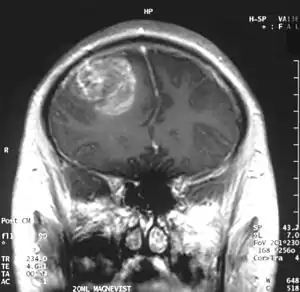

| Coronal MRI with contrast of a glioblastoma in a 15-year-old male | |